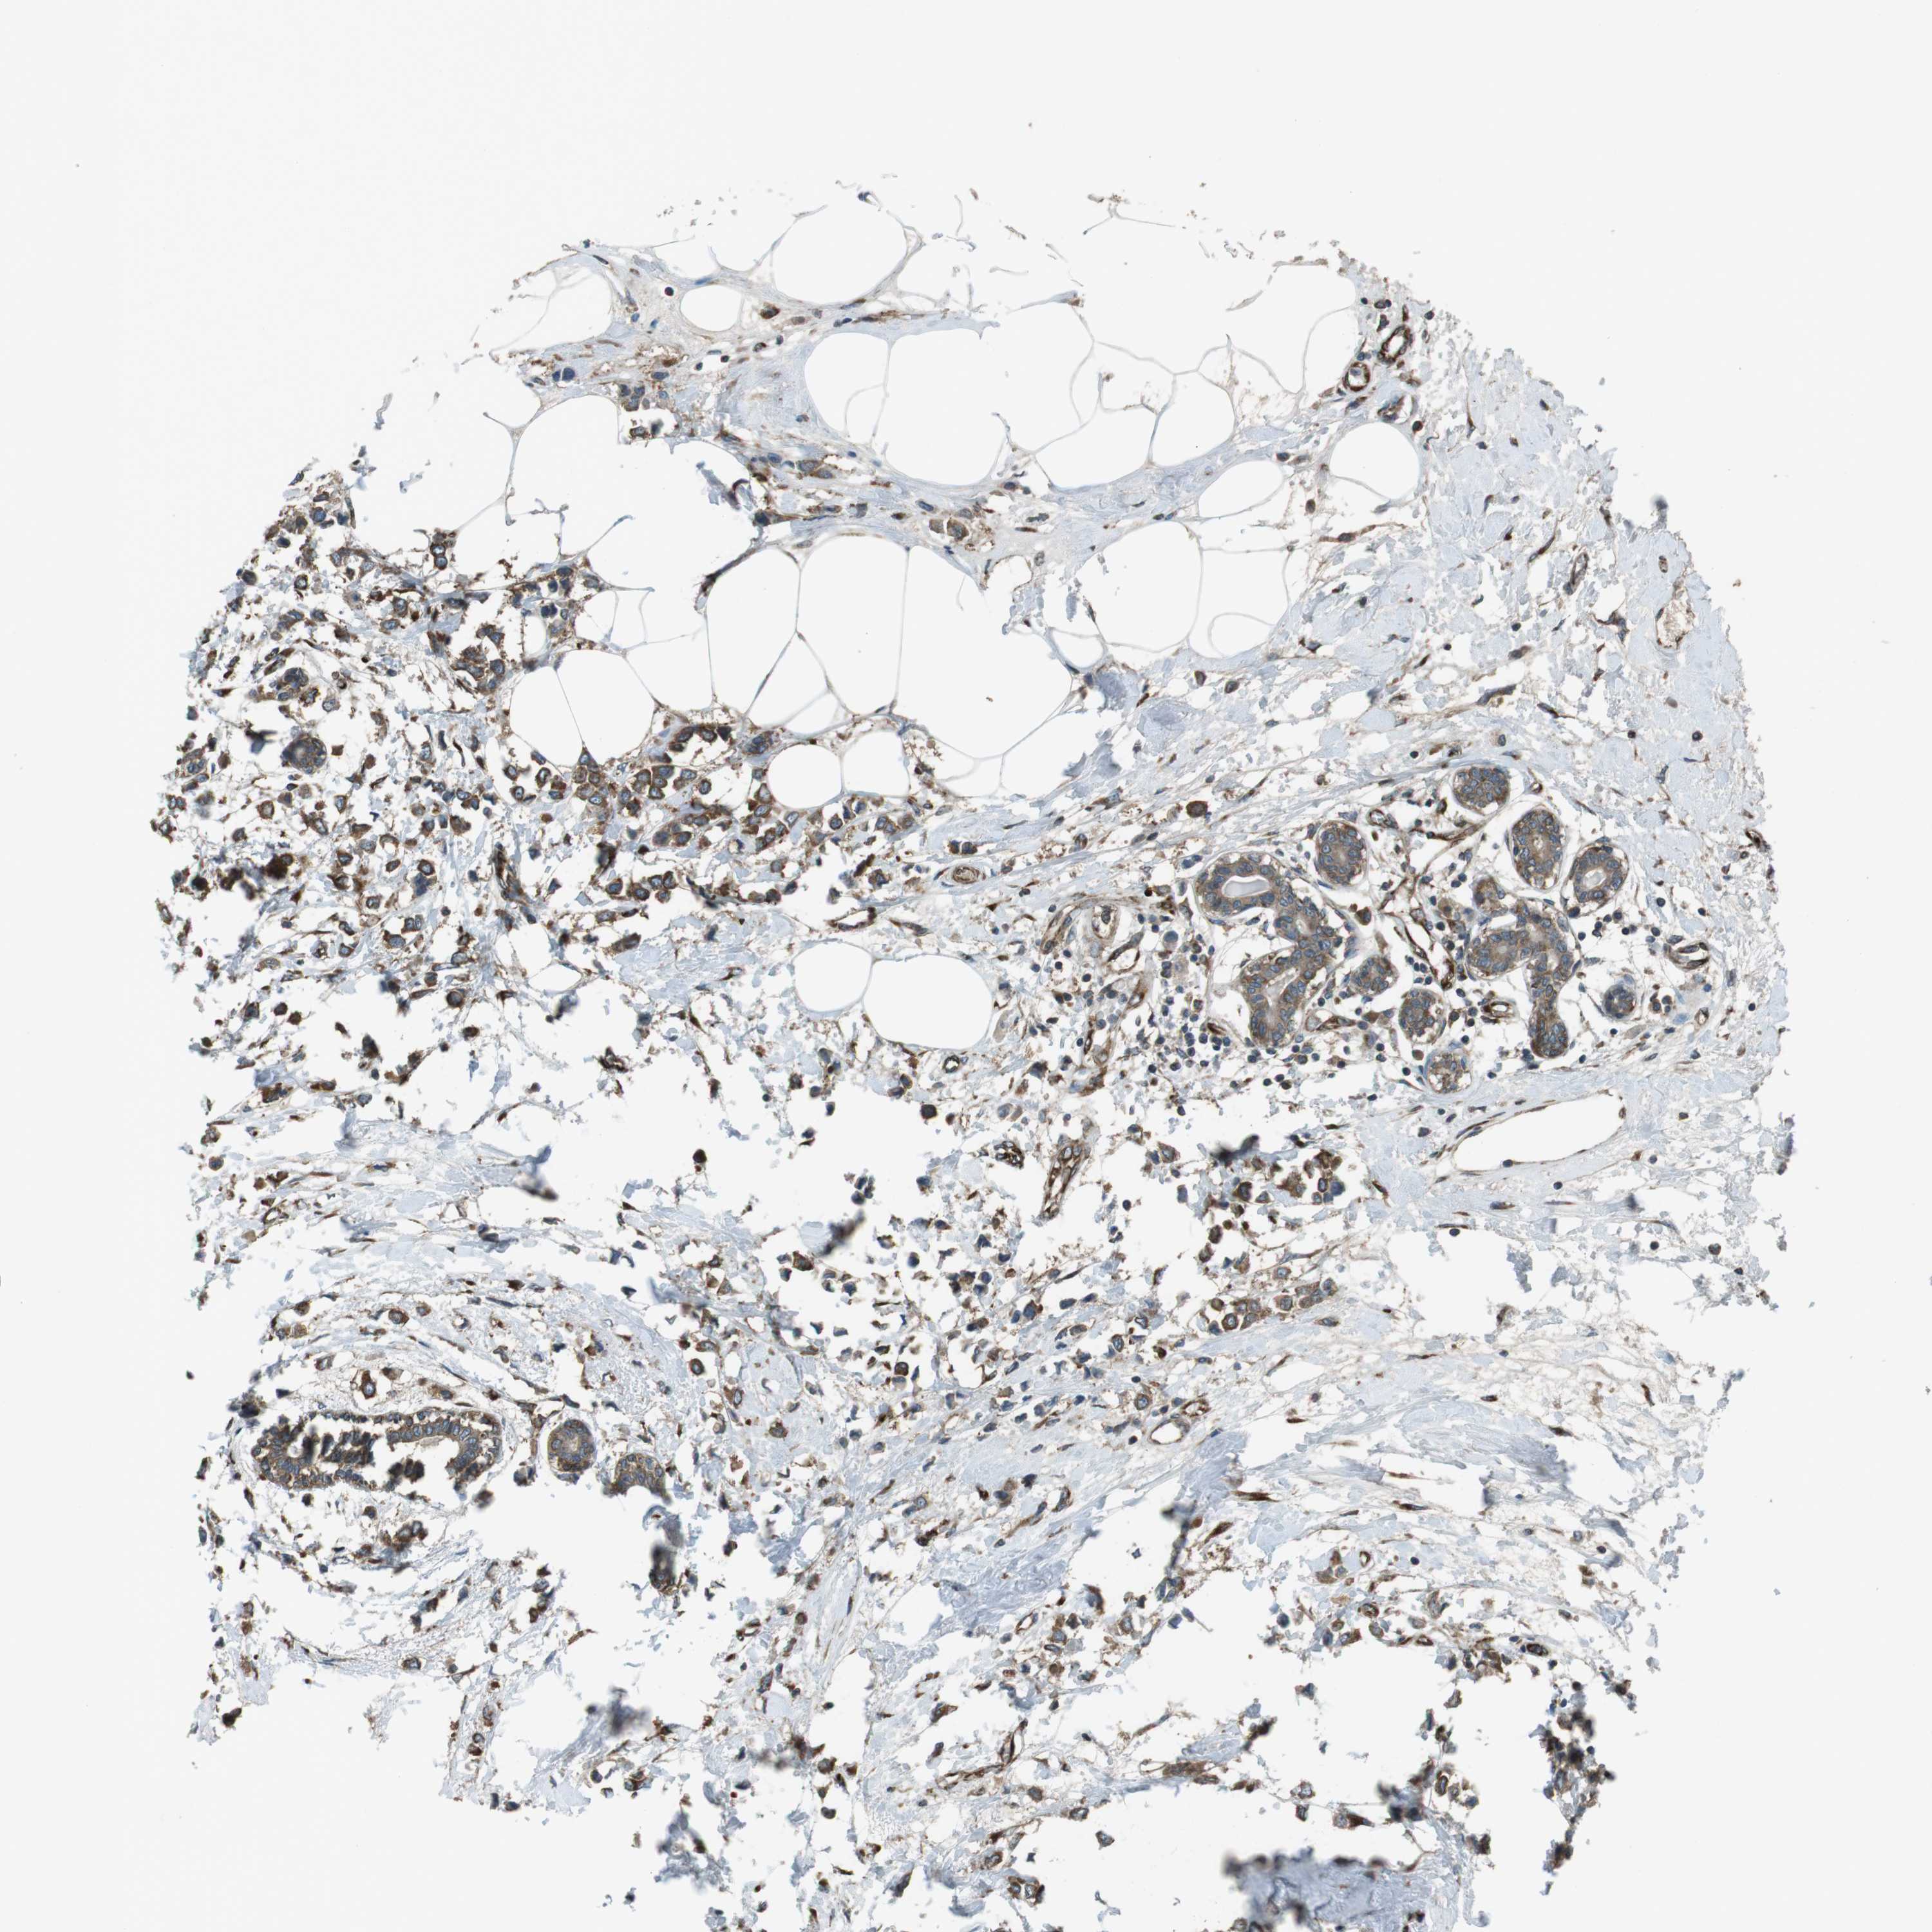

CANCER BREAST CANCER Show tissue menu

BRCA TCGA BRCA VALIDATION PROTEIN EXPRESSION